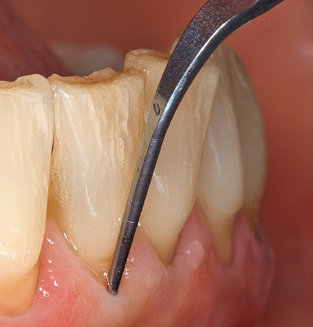

Unerlässlich für die UPT implantat prothetisch versorgter Patienten sind natürlich Arbeitsspitzen für die Reinigung von Implantatoberflächen. Der Implantatreinigungsaufsatz des hier verwendeten Systems zeichnet sich dabei durch eine spitz zulaufende sechskantige konische Form aus. Dieses Design erlaubt ein leichtes atraumatisches Eindringen in die periimplantäre Tasche und zeigt eine gute Reinigungsleistung (Abb. 7).